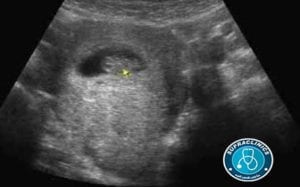

شكل الجنين فى الشهر الثانى

يكون حجم الطفل أثناء الحمل فى الشهر الثانى في حجم ثمرة التوت وربما يبدو بشكل أكثر غرابة، يكون شكل الجنين فى الشهر الثانى كالأتي:

أنبوب ملتوي مع نهاية تلك الأنبوب تكون رأس الجنين والأخر قدميه وما يصل الطرفين يكون هو الحبل الشوكي.

تبدء الأنسجة المسئولة عن تكوين القلب في التكون والضرب ويُمكن سماعها عن طريق فحص الموجات فوق الصوتية “CT Scan”.

ويُمكن سماع تلك الأصوات في الاسبوع السادس من الحمل، كما أن أطراف الطفل تبدء في التكون وتكون علي شكل مجاديف.

يبدء الجهاز التناسلي للطفل في التكون ولكن لا يُمكن رؤيتها،

في نهاية الشهر الثاني من الحمل تكون نمت إلي طول 2 بوصة وباقي الأجهزة الرئيسية تكون قد بدأت في التكون.